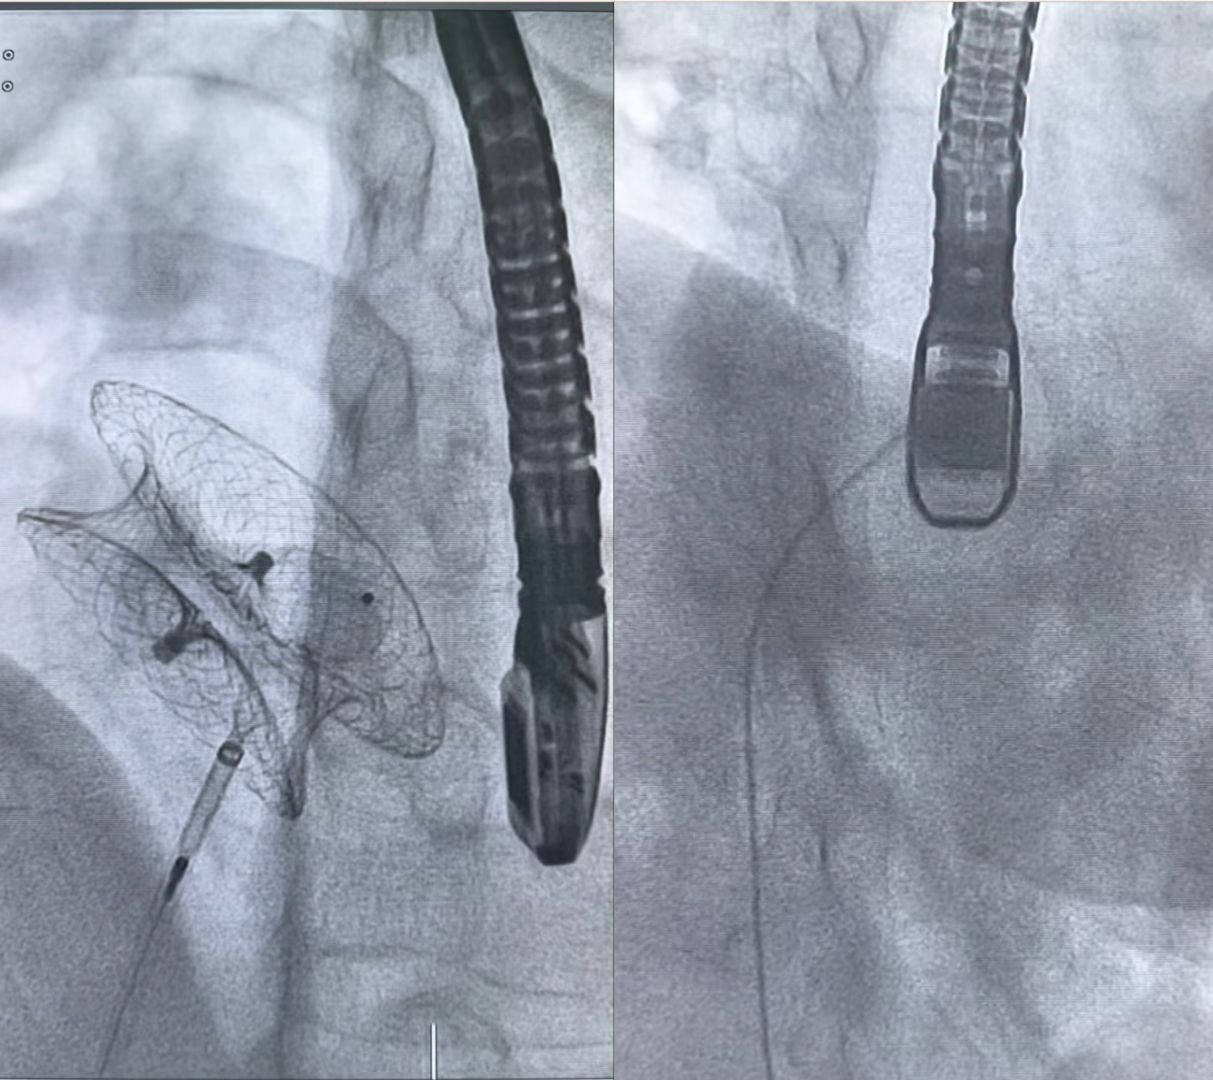

Trước tình huống trên, phương án thường được lựa chọn là phẫu thuật tim mở để lấy dụng cụ cũ và vá lại lỗ thông. Tuy nhiên, sau khi cân nhắc kỹ lưỡng và tham khảo thêm kinh nghiệm từ đồng nghiệp, ê-kíp quyết định thử một hướng tiếp cận khác: sử dụng thêm một dụng cụ để bít lỗ thủng tồn dư.

Thách thức lớn nhất là nguy cơ làm bong lớp nội mạc bám trên dụng cụ cũ, có thể gây tắc mạch, thậm chí đột quỵ. Sau khi đánh giá kỹ, ê-kíp nhận định có thể đưa dụng cụ mới qua vị trí thủng mà không làm ảnh hưởng đến cấu trúc xung quanh.

Thủ thuật được tiến hành với kỹ thuật tạo vòng loop động – tĩnh mạch, đưa dụng cụ Vascular plug II kích thước 12 mm vào bít kín hoàn toàn lỗ thủng. Toàn bộ quá trình diễn ra trong khoảng 1 giờ.